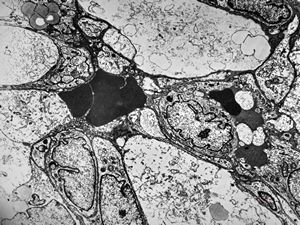

F,49y. | purulent meningitis- meningococcal v.s.

F,49y. | purulent meningitis- meningococcal v.s.

F,49y. | purulent meningitis- meningococcal v.s.